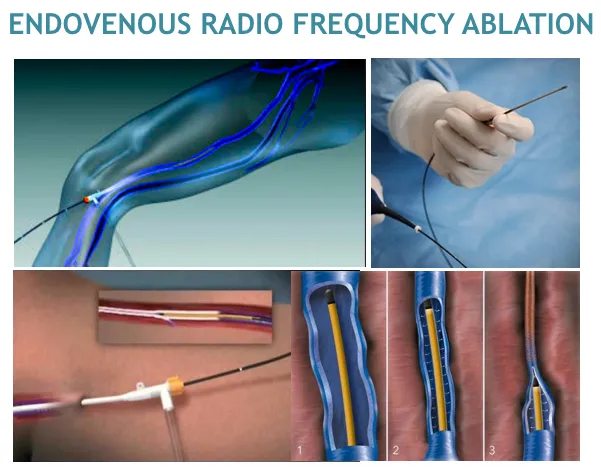

3. 静脉腔内热消融 (endovenous thermal ablation, EVTA)

国际上公认,伴有静脉曲张或静脉疾病症状或体征的N2静脉干功能不全的一线治疗是静脉内热消融(EVTA)。这通常通过静脉内激光消融(EVLA)或射频消融(RFA)进行,但也有其他形式的EVTA,如蒸汽静脉硬化(SVS)和静脉内微波消融(EMWA)

EVLA和RFA有多种不同的形式。在最基本的形式中,EVLA纤维可以是裸头的、套头的(减少静脉壁接触)、郁金香头的(防止所有静脉壁接触)或径向的(将激光能量侧向直接引导到静脉壁)——随着单环或双环径向纤维的出现。RFA装置可以是单极或双极的,通过电流通过静脉壁在射频频率引起加热,或部分,在装置的末端的金属线圈被射频电流加热,热量通过简单的传导进入静脉壁。